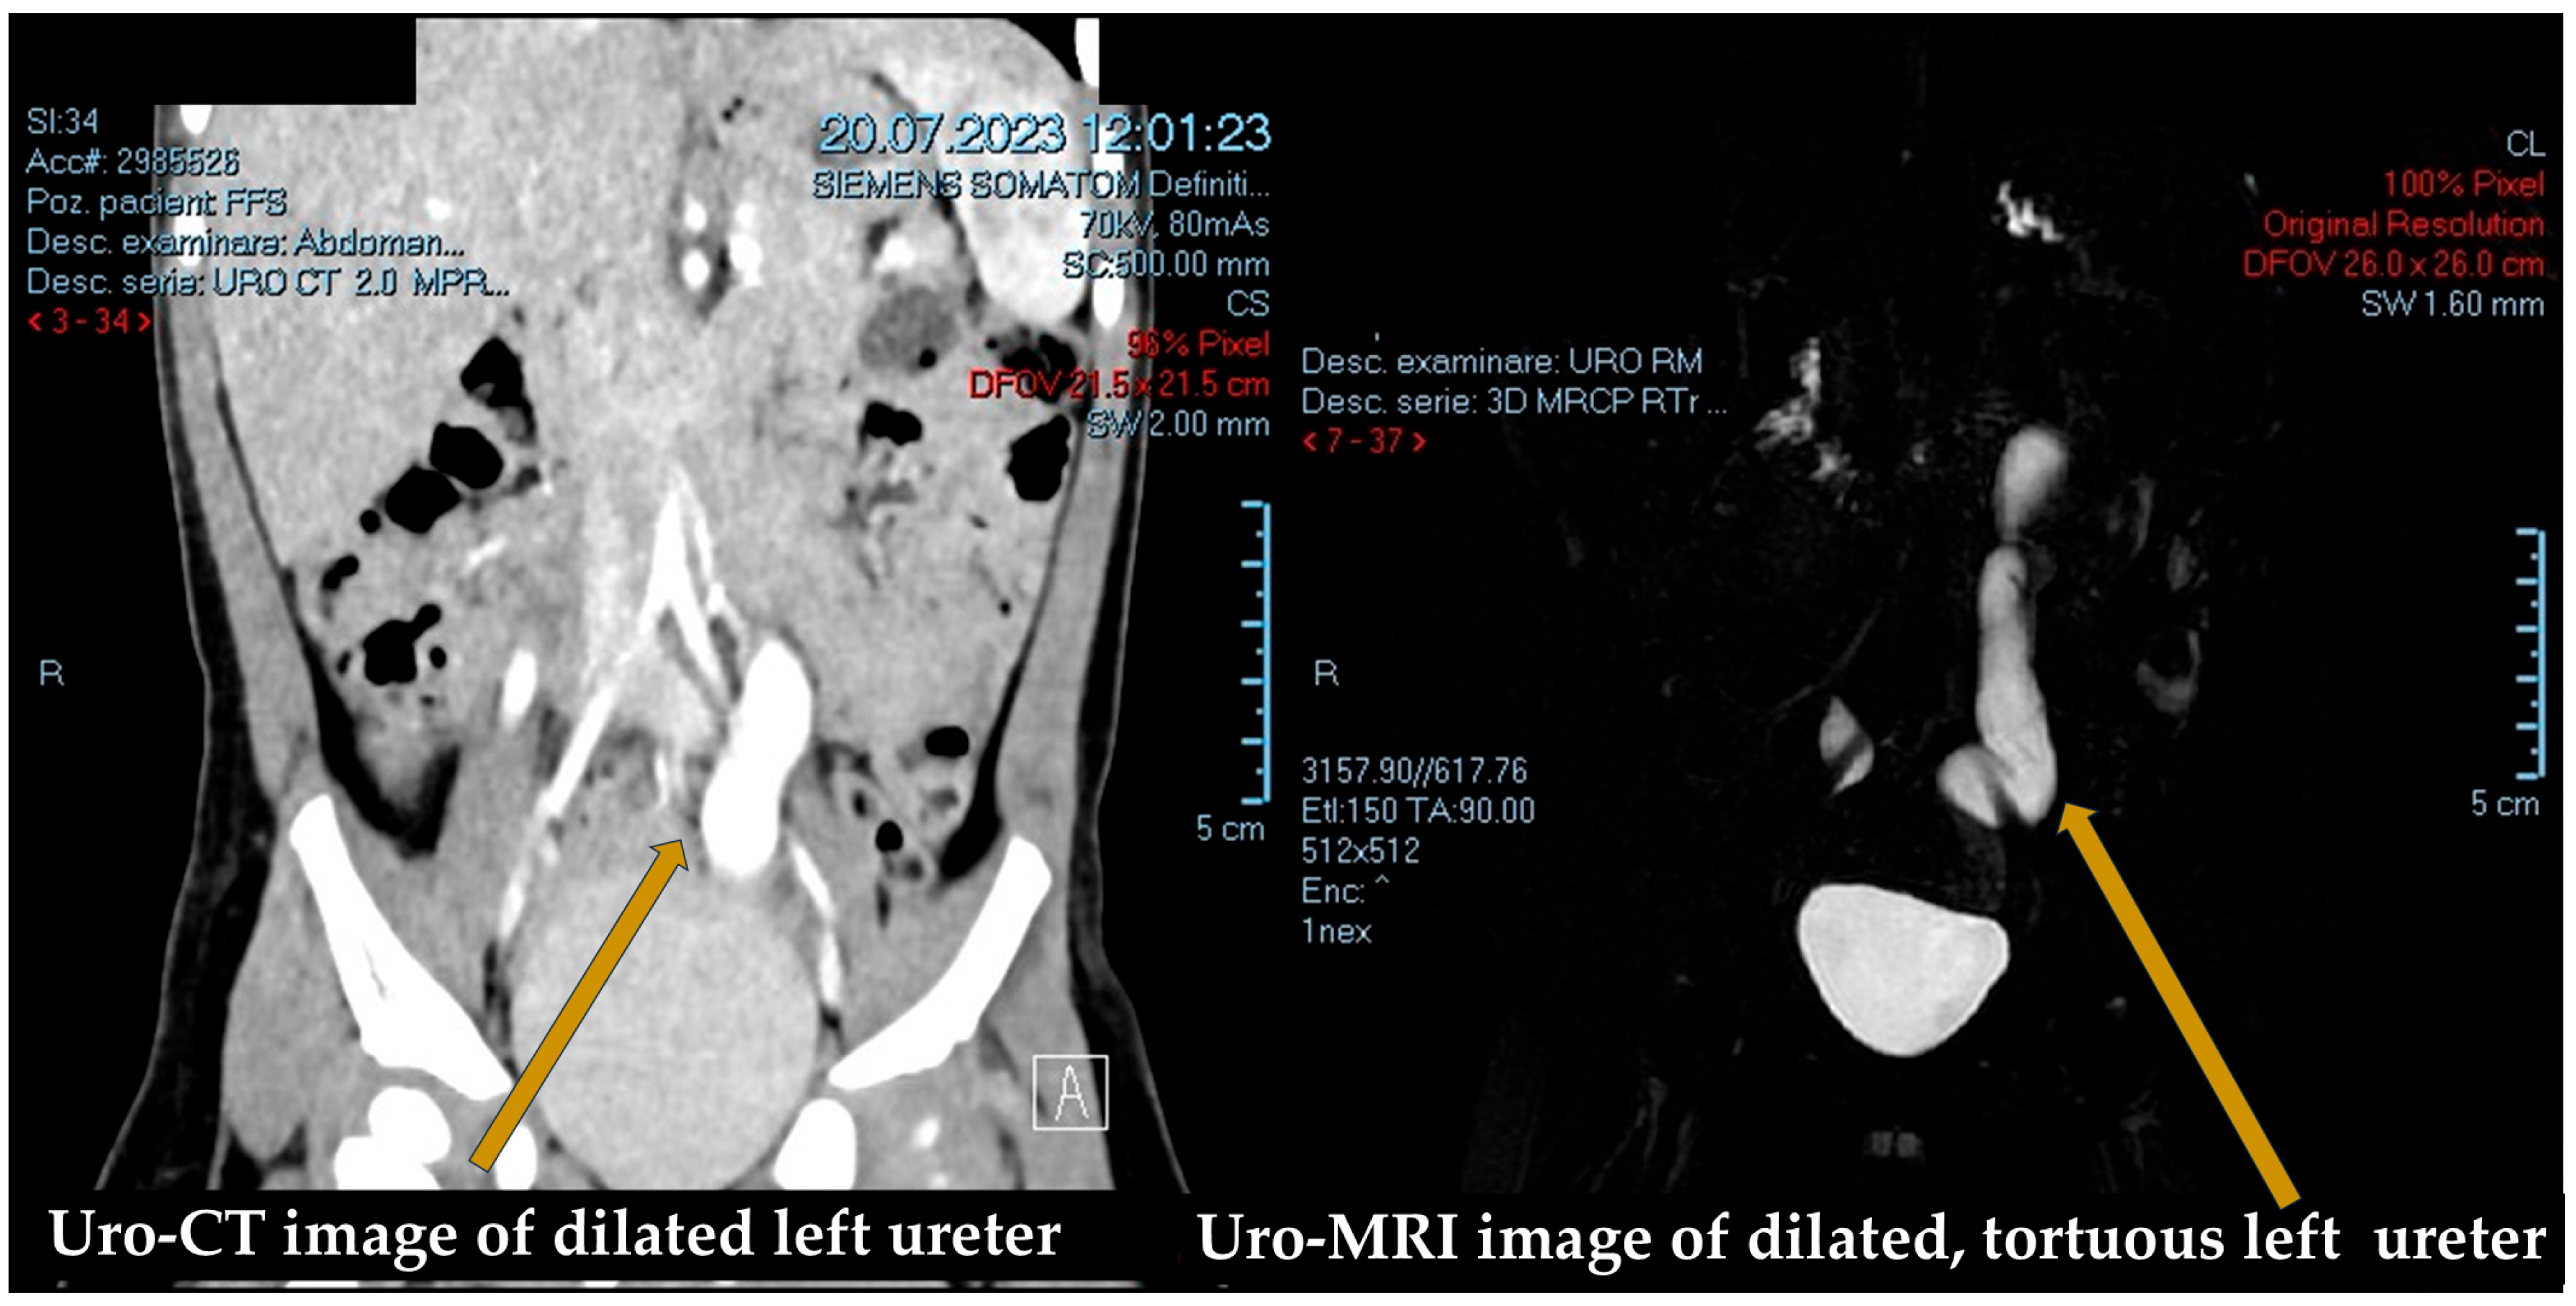

2.2. Diagnostic Evaluation (Figure 1 and Figure 2)